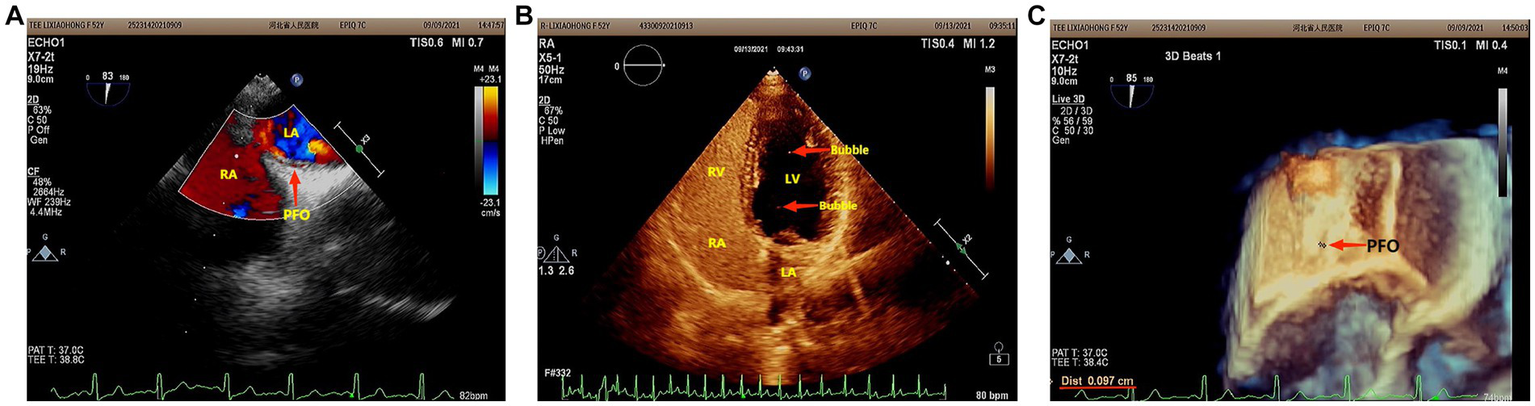

However, she presented with cyanosis and was found to be hypoxic, with an oxygen saturation of 94.48% on room air. The arterial blood gas showed an oxygen tension of 65.64 mmHg. Routine blood tests, biochemistry, ESR, thyroid function, cortisol, female tumor examination, chest CT, ultrasound of deep and intermuscular veins of both lower limbs, and Holter monitor were normal. D-dimer quantitation was 0.6 mg/L (0–0.55), and prolactin was reported as 42.86 ng/mL. Echocardiography: mild aortic, mitral, and tricuspid regurgitation. Agitated saline contrast echocardiography was positive (RLS grade 1; Figure 1). Transesophageal echocardiography showed a fossa ovoid fissure, approximately 0.9 mm wide (occasionally stellate shunt; Figures 1B,C). Additionally, an MRI image showed bilateral frontal lobe chronic small ischemic focus (Figure 2), and MRA results were normal. EPQ: P 62, N 46, E 64, L 44. SCL-90: the total score was 205, the number of positive symptoms was 65, anxiety was 2.9, phobia was 2.67, somatization was 2.33, psychosis was 1.9, obsessive–compulsive was 2.4, depression was 2.38, and other symptoms were 2.57. HAMA:26, HAMD24:31. These indicated that the patient had severe anxiety and depression accompanied by hypoxemia. Medical history, along with symptoms, signs, and examination showed that hypoxemia and cyanosis were not caused by arteriovenous fistula, pneumonia, pulmonary embolism, thrombophlebitis, pericarditis, right heart failure, severe shock, Raynaud’s disease, occlusive vasculitis, methemoglobin due to nitrite, sulfur-containing drug intake, or ampicillin poisoning. Acute nausea and vomiting may have been related to venlafaxine’s sudden withdrawal. Therefore, the patient was diagnosed with anxiety disorder, depressive episodes, and hypoxemia (ICD-10). As a result, she was prescribed paroxetine and oxazepam to improve her anxiety, depression, and insomnia. Olanzapine can improve physical symptoms such as nausea and vomiting and help to improve insomnia, anxiety, and depression (16). Meanwhile, oxygen inhalation was carried out. When other structural abnormalities or pathological changes in the lungs and heart were ruled out, we found the patient suffered from PFO (Figure 1). Interestingly, only 2 days later, when insomnia, shortness of breath, nausea, dizziness, and anxiety symptoms improved, PaO2 increased to 89.47 mmHg. Furthermore, cyanosis disappeared, and D-dimer returned to normal (as is widely understood, a hypercoagulable state is associated with severe anxiety (17)). Thus, we stopped oxygen inhalation, and PaO2 did not decrease (Table 1). Based on the above results, we speculated that physical stress (nausea, shortness of breath, etc.) and emotional stress are major stressors for patients, leading to cyanosis and acute, transient hypoxia due to increased right-to-left shunt. When anxiety, depression, nausea, and other stressors were relieved, the right-to-left shunt may have been small, and acute hypoxia was eventually improved. Six months later, the patient insisted on low oral doses of paroxetine and olanzapine, felt stable, and no longer appeared to present with cyanosis or hypoxia.

Figure 1. (A) Agitated saline contrast echocardiography showed that the maximum number of bubbles in a single frame was less than 10 bubbles (RLS 1) in three cardiac cycles after the Valsalva maneuver. (B) Two-dimensional echocardiography of the transesophageal heart showed that there was a 0.9 mm wide fissure echo in the middle ovoid fossa of the atrial septum. (C) Three-dimensional echocardiography of the Transesophageal Heart: After the Valsalva maneuver, the width of the ovoid fossa of the atrial septum was approximately 0.9 mm (star-like shunt was occasionally seen).